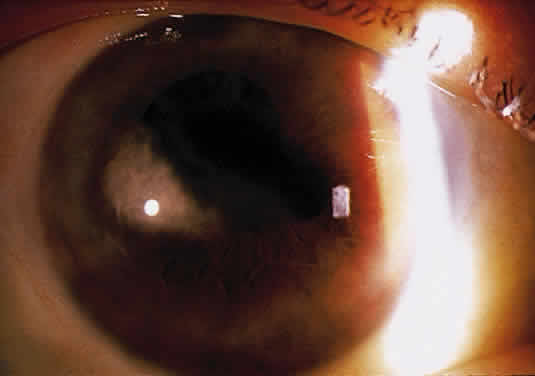

Herpetic keratouveitis can occur in association with any form of herpetic keratitis. Anterior chamber inflammation that accompanies epithelial disease is thought to be caused by reflex irritation and is characteristically both mild and transient. However, the iridocyclitis that invariably accompanies necrotizing disease tends to be much more severe, and is not necessarily correlated with the apparent severity of the keratitis. Indeed, although uveitis dominates the clinical picture in some cases of ocular HSV, subtle corneal findings are limited to faint cellular infiltration of the stroma. Uveitis that accompanies necrotizing disease is typically granulomatous and often recurrent. In more severe cases, perilimbal injection is marked, and the cornea can become thickened and edematous. Dense, fibrinous flare with heavy, anterior chamber cell and medium-sized white keratic precipitates may be distributed widely over the endothelium (Fig. 2). A hypopyon and synechiae can form, and elevated intraocular pressure that exacerbates this often painful uveitis may develop. Marked dilation of iris blood vessels and spontaneous hyphemas sometimes occur. Episodes of inflammation are frequently marked by progressive iris atrophy and sphincter damage, leading to corectopia and anisocoria (Figs. 3 and 4).